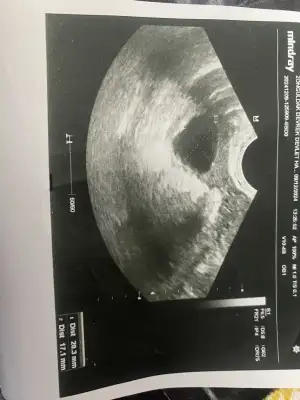

Kızlar merhaba 21 kasım aşılamam yapılmıstı 14 gün adet olsun adet bitimi şehir değişikliği nedeniyle kendi doktoruma gidemedim baska bir dr gittim kontrol etti ultrasyon kagıdı verdi hiçbirşey dememe fırsat vermedi herşey normal dedi gönderdi ama benim aklıma takıldı bu yumurtamaıdır kist midir anlayan varsa yardımcı olurmusunuz